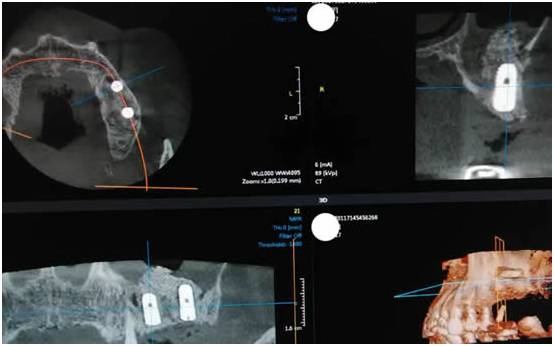

图一:术前ct检查(上颌窦底只有不到2毫米厚度、上颌窦黏膜有炎症性水肿)

图五:术后CT(植入的骨粉以每个月一个毫米的速度变成自己的骨头,半年后他就可以有可以媲美真牙的种植牙了,就可以吃香喝辣了)

图六:术后CT

1、上颌窦只有不到两个毫米厚度的骨头了

2、上颌窦黏膜有炎症性水肿

3、手术30分钟完成,种植体是韩国奥齿泰,直径5.0毫米,长度是11.5毫米。